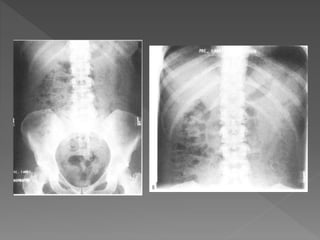

X ray films 1)Pre contrast 2) 5 mins 3) 25 mins 4) Post void

 The plainfilm demonstrates calcification within distended upper pole calyces